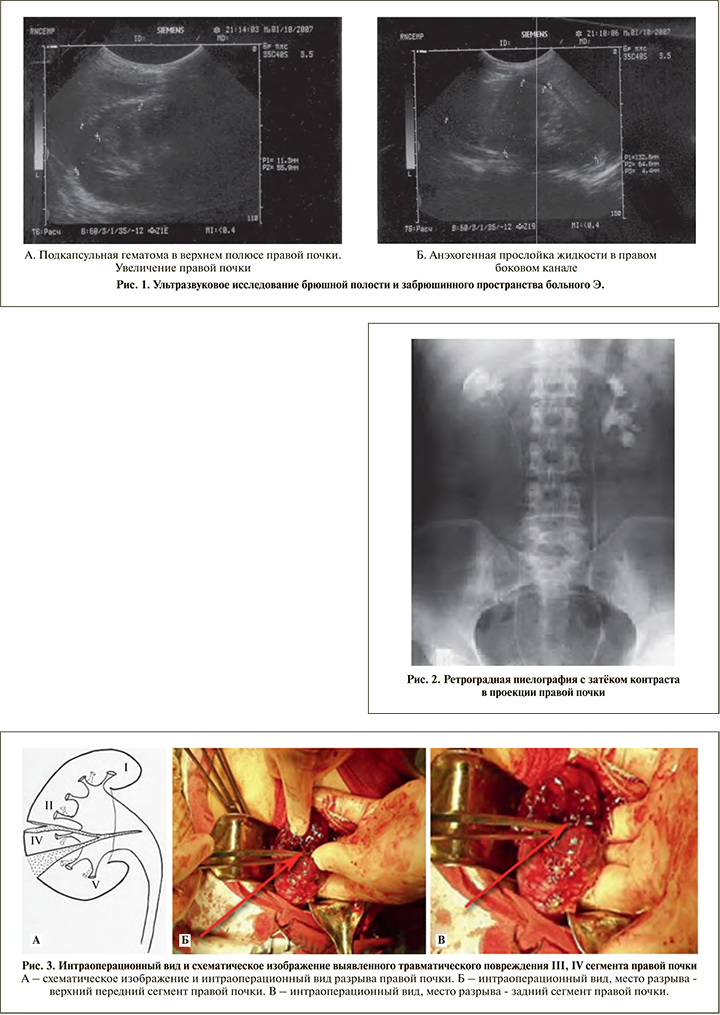

Выполнено ультразвуковое исследование (УЗИ) брюшной полости и забрюшинного пространства (рис. 1), при этом установлен факт увеличения размера правой почки, резкого ограничения ее подвижности, контуры почки нечеткие, в области верхнего полюса правой почки определяется наличие подкапсулярной гематомы (рис. 1А). В брюшной полости выявлено наличие анэхогенной прослойки жидкости в правом боковом канале (рис. 1Б), что свидетельствовало о закрытой травме живота и забрюшинного пространства, травматическом повреждении паренхимы почки.

Больному выполнена ретроградная пиелография, при которой отмечается затек контрастного вещества в проекции правой почки (рис. 2).

Интраоперационный вид и схематическое изображение выявленного травматического повреждения III, IV сегментов правой почки представлены на рис. 3.

Интраоперационно установлен неполный разрыв правой почки, что послужило основанием для выполнения органосохраняющего вмешательства с восстановлением поврежденных структур почки, наложены П-образные швы атравматической нитью Викрил 3,0 (рис. 4).